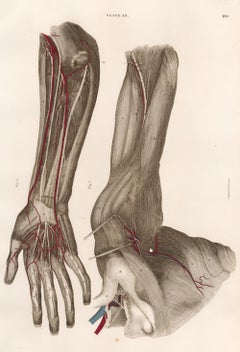

Artist: John Lizars

Anatomical Engraving of a Human Arm

By John Lizars

Located in New York, NY

Original color printed engraving, embellished by hand from "Anatomical Plates of the Human Body." Edinburgh: 1822-27. John Lizars was a professor of surgery at the Royal College of ...